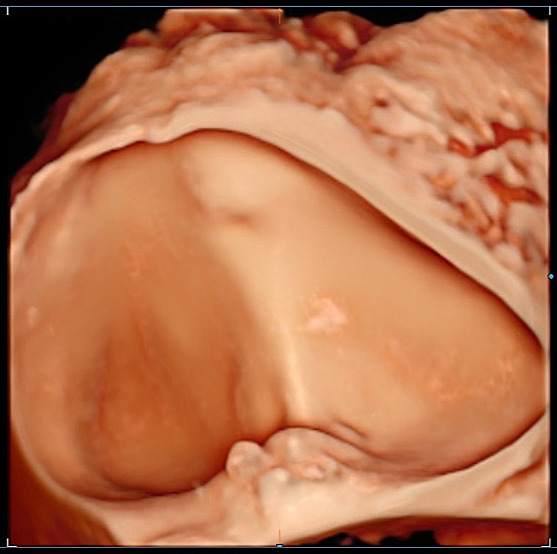

- Macrocystic lesion in the myometrium without contact with JZ or uterine cavity. Some lesions appear to be exclusively macrocystic (greater than 10 mm in diameter), consisting of one or more large, well-defined hypoechogenic cysts within the myometrium (Figure 5), typically surrounded by an echogenic rim. Retroacoustic enhancement is observed behind the central part of the cyst, while posterior to the lateral part, edge shadowing can also be present. Some of these lesions show other direct features of adenomyosis, with the most likely hypothesis being invasion from the uterine cavity with progressive development of one or more microcysts within the ectopic endometrial tissue. In the absence of direct features, de-novo development of a cystic lesion within the myometrium is more probable. The cyst content may exhibit a ground-glass or hemorrhagic appearance.

- Accessory cavitated malformation (ACUM) in the outer myometrium. ACUM is defined as a cavitated lesion, surrounded by a myometrial mantle, in continuity with the anterolateral uterine wall and located beneath the insertion of the round ligament and the interstitial portion of the Fallopian tube (Figures 6 and 7). The uterine cavity should be normal, in contrast to that in other uterine anomalies such as a rudimentary horn and its associated unicornuate hemiuterus.25,26 The lesions have a predominantly ground-glass echogenicity, with a smooth inner lining, corresponding to hemorrhagic cyst content and functional surrounding endometrium, respectively. ACUMs have been described using different terms ranging from ‘juvenile cystic adenomyosis’ to ‘uterus-like mass’. It is hypothesized that this is a newly recognized type of Mullerian anomaly, other theories suggesting a specific form of metaplasia.27,28